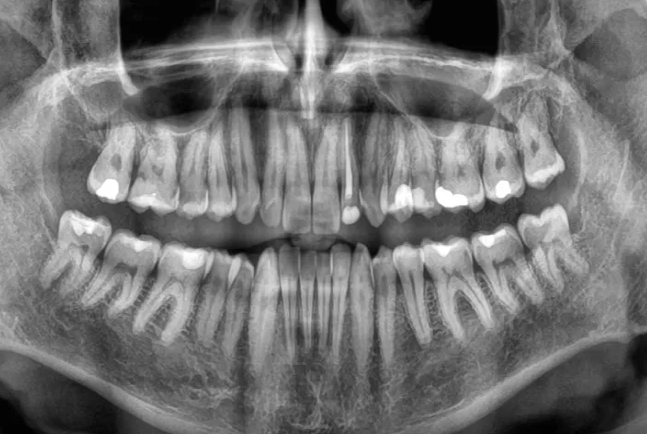

Diş itkisi ölüm riskini artıra bilər -ARAŞDIRMAYeni bir araşdırma göstərib ki, yaşlı insanlarda dişlərin sürətlə itirilməsi ölüm riskinin artması ilə əlaqəlidir. Çinli alimlər 3,5 il ərzində 8073 yaşlı insanı izləyərək belə nəticəyə gəliblər.

Lent.az "sciencealert.com" portalına istinadla xəbər verir ki, tədqiqatın nəticələrinə görə, dişlərin itirilmə sürəti nə qədər yüksəkdirsə, bütün səbəblərdən ölüm riski də bir o qədər artır. Bu əlaqə yaş, cins, təhsil, içki və məşq vərdişləri kimi digər amillər nəzərə alındıqdan sonra da qalır. Mütəxəssislər bildirirlər ki, dişlərin itirilməsi birbaşa ölümə səbəb olmur, lakin diş itkisinə yol açan sağlamlıq problemləri, məsələn, iltihab, pis qidalanma və ürək xəstəlikləri ömrü qısalda bilər. Alimlər diş itkisinin insanın ümumi sağlamlıq vəziyyətini qiymətləndirmək üçün göstərici kimi istifadə oluna biləcəyini vurğulayırlar. Həkimlər dişlərin qorunması üçün müntəzəm diş həkimi müayinəsini, gündə iki dəfə fırçalamağı və siqaretdən uzaq durmağı tövsiyə edirlər.

Araşdırma "BMC Geriatrics" jurnalında dərc olunub.